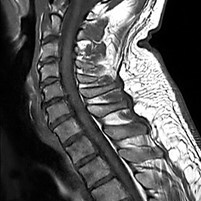

Die MRT (Magnetresonanztomographie), auch Kernspintomographie genannt, ist eine Untersuchung in einem Magnetfeld und benötigt keine Röntgenstrahlen. Mit ihr können alle Körperregionen überlagerungsfrei dargestellt werden. Wir führen hier die MRT fast aller Körperregionen, Organe und Blutgefäße durch.